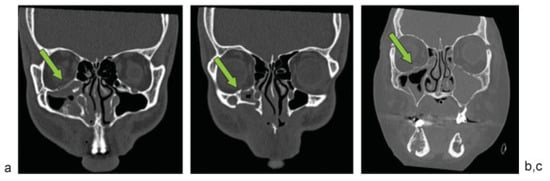

Figure 3.

Limits of the orbital floor anteriorly are bounded medially by the septum between the ethmoid and maxillary sinuses at point A, and laterally by the most inferior and lateral aspect of the zygomatic portion of the orbital floor at point B.

Figure 4.

Limits of the orbital floor posteriorly are bounded medially by the septum between the ethmoid and maxillary sinuses at point A, and laterally by the medial edge of the inferior orbital fissure at point C.